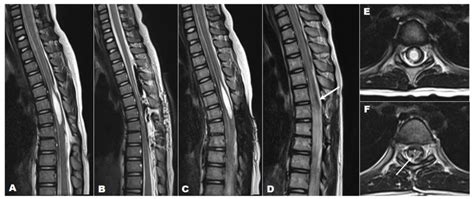

Tethered Cord MRI plays a pivotal role in the diagnosis of tethered cord syndrome. This imaging technique uses magnetic fields and radio waves to produce detailed images of the spinal cord and surrounding structures. Unlike traditional MRI, Tethered Cord MRI focuses specifically on the spinal cord, providing high-resolution images that can detect even the slightest abnormalities.

One of the key advantages of Tethered Cord MRI is its ability to visualize the spinal cord in multiple planes. This allows radiologists to get a comprehensive view of the spinal cord and identify any areas where it may be tethered. The images obtained from Tethered Cord MRI are also highly detailed, making it easier to pinpoint the exact location and extent of the tethering.

After the Tethered Cord MRI procedure, the images will be reviewed by a radiologist who specializes in interpreting MRI scans. The radiologist will look for signs of tethered cord syndrome, such as:

• Abnormal Attachments: The spinal cord may be attached to surrounding tissues, such as the dura mater or vertebrae, in an abnormal manner.

• Thickened Filum Terminale: The filum terminale is a thin, fibrous structure that anchors the spinal cord. In tethered cord syndrome, this structure may be thickened or shortened.

• Spinal Cord Stretching: The spinal cord may appear stretched or elongated, indicating that it is being pulled down by the tethering.

• Other Abnormalities: The radiologist may also look for other abnormalities, such as spinal cord tumors, cysts, or malformations, that could be contributing to the symptoms.